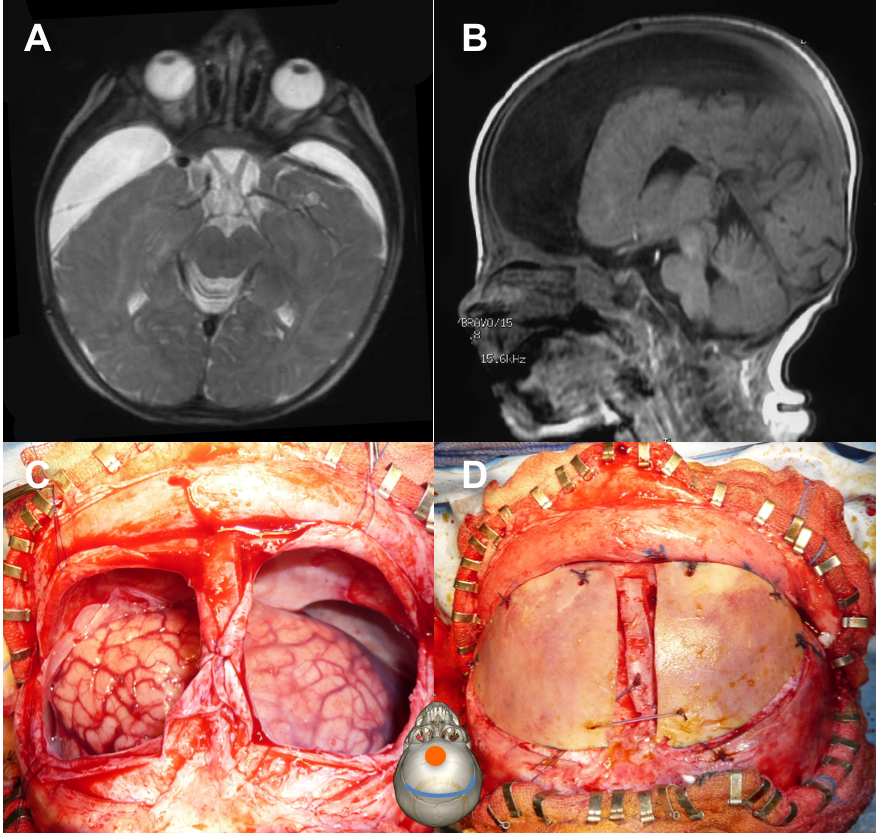

dans certains cas cependant, en raison notamment d’une atrophie cérébrale associée, le cerveau ne peut pas se ré-expandre et des membranes sous-durales se forment, s’épaississent, et enserrent le cerveau dans une coque qui peut devenir rigide voire s’ossifier.

technique

- par un abord coronal, on expose la région fronto-pariétale paramédiane en sous-galéal

- exposition sous-periostée des 4 coins osseux et désinsertion de la fontanelle

- craniotomie aux ciseaux ou au craniotome, les volets peuvent être cassés en charnière et pédiculés sur une fracture en bois vert

- ouverture en croix de la dure-mère et dissection extra-capsulaire

- ouverture et résection de la coque externe puis de la coque interne

- remise en place d’un drainage sous-duro-péritonéal compétent

- fermeture durale, osseuse et cutanée